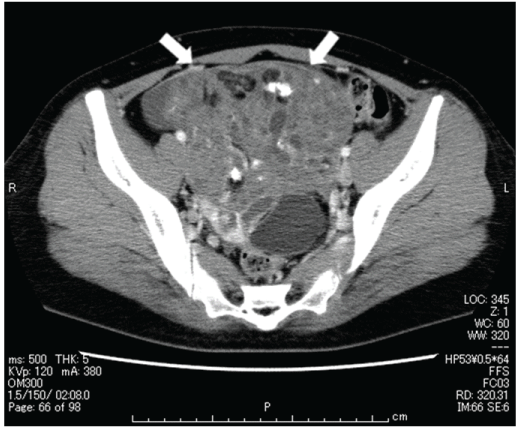

Figure 4: CT findings of two sites of recurrent tumors before the radical total resection.The recurrent tumors are indicated by white arrows. (a) Right subphrenic space (b) Pouch of Douglas

Four years and five months after the appearance of peritoneal dissemination, and following the delivery of her fourth child, the patient finally decided to undergo radical surgery and came to our hospital. CT scan at this time revealed the enlargement of all existing peritoneal dissemination, but there were no new lesions (Figure 4). She then underwent total abdominal hysterectomy, left salpingo-oophorectomy, resection of the peritoneal dissemination, extended right hepatectomy, and lower anterior resection of the rectum, with the complete removal of the lesions (Figure 5). The disseminated lesions between the right hepatic lobe and the diaphragm had a clear border, but strongly adhered to the diaphragm and invaded the liver. The adhesions were difficult to separate, the partial diaphragm and right hepatic lobes were resected to perform the total resection of the tumor. The total duration of the surgery was 13 h and 38 min, including 7 h of resection of the subdiaphragmatic dissemination; the total blood loss was 1,311 mL. The pathological diagnosis was mature teratoma without malignant findings, thus confirming the initial suspicion of GTS (Figure 6). One year and six months later, there were no signs of recurrence.